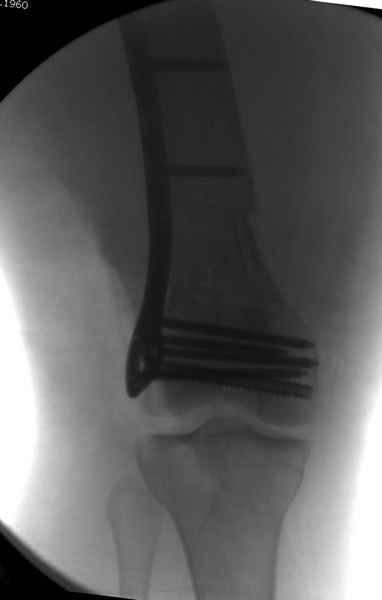

Re: Сегментарный перелом бедра - открыто или закрыто?

При наличии различных имплантов, любые варианты: слева (полу) открытым - мининвазивным, а справа закрытым интрамедуллярным методом, его считаем более чем приемлемым для фиксации данных переломов.

Проксимальная и дистальная блокировка, независимо от техники введения штифта, ретроградно или антеградно, гарантирует сращение сегментарных переломов бедра без укорочения. Штифты диаметром 12 мм с блокировкой сверху и вниз двумя шурупами выдерживают вес 75 кг больного, что позволяет раннюю профилактику контрактур.

Из-за вариабельности установки дистальных шурупов и возможности перкутанного введения проксимально предпочитаем DePuy Polyax, хотя на сегодняшнем маркете множеств вариантов фиксации дистального бедра перкутанном методом.